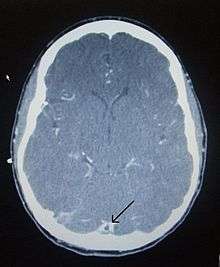

There are various neuroimaging investigations that may detect cerebral sinus thrombosis. Cerebral edema and venous infarction may be apparent on any modality, but for the detection of the thrombus itself, the most commonly used tests are computed tomography (CT) and magnetic resonance imaging (MRI), both using various types of radiocontrast to perform a venogram and visualise the veins around the brain.[1]

Computed tomography, with radiocontrast in the venous phase (CT venography or CTV), has a detection rate that in some regards exceeds that of MRI. The test involves injection into a vein (usually in the arm) of a radioopaque substance, and time is allowed for the bloodstream to carry it to the cerebral veins - at which point the scan is performed. It has a sensitivity of 75-100% (it detects 75-100% of all clots present), and a specificity of 81-100% (it would be incorrectly positive in 0-19%). In the first two weeks, the "empty delta sign" may be observed (in later stages, this sign may disappear).[5]